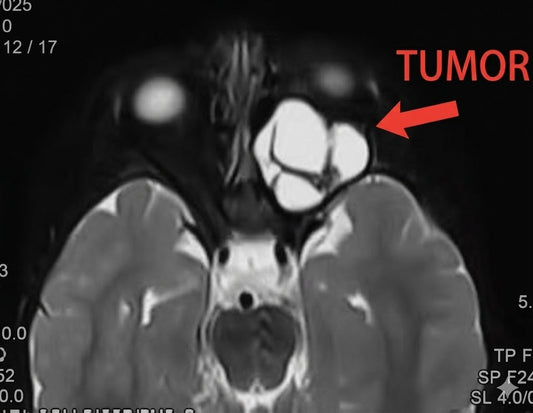

Professor Yu Chunjiang: A Leading Expert in Sku...

Professor Yu Chunjiang is a pioneering neurosurgeon specializing in skull base surgery, with over 11,000 successful intracranial tumor surgeries. He has significantly advanced the field through his research, international collaborations,...